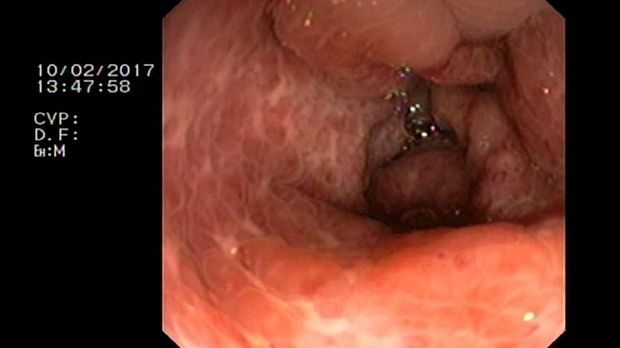

2 мл ( это мин сум, а мы делаем до 10 мл 3% перекись+200 мл физ раствора